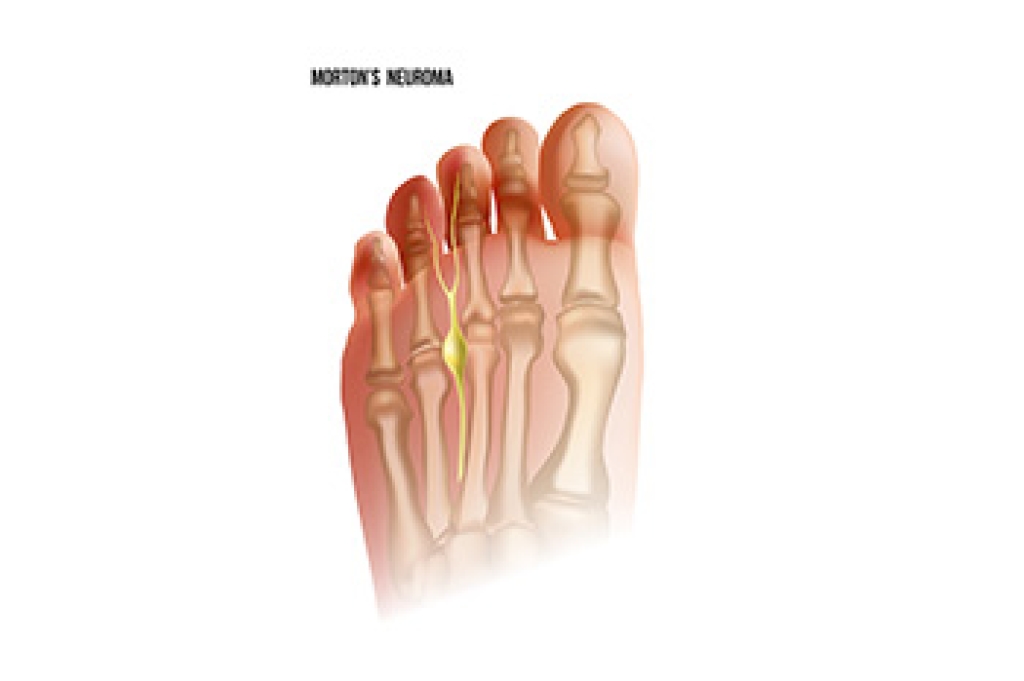

The nerve found between the third and fourth toes can be affected by a foot condition known as Morton’s neuroma. This is an ailment that compresses or irritates the nerve and is considered to be benign. The majority of patients who develop Morton’s neuroma have severe pain and discomfort, and it can be difficult to walk. Morton's neuroma may be common in women who frequently wear high heels. These types of shoes have limited room in the toe area and this can cause the toes to shift toward each other, affecting the nerve. The pain is often felt in the ball of the foot and can be noticed while standing and walking. Additionally, a burning or tingling sensation can affect the toes, and it may feel like there is a small pebble in the shoe or sock. If you have pain in this area of your foot, it is suggested that you seek the counsel of a podiatrist who can perform a diagnosis and offer the proper treatment options.

Morton’s Neuroma

Morton's neuroma is a painful foot condition that commonly affects the areas between the second and third or third and fourth toe, although other areas of the foot are also susceptible. Morton’s neuroma is caused by an inflamed nerve in the foot that is being squeezed and aggravated by surrounding bones.

What Increases the Chances of Having Morton’s Neuroma?

- Ill-fitting high heels or shoes that add pressure to the toe or foot

- Jogging, running or any sport that involves constant impact to the foot

- Flat feet, bunions, and any other foot deformities

Morton’s neuroma is a very treatable condition. Orthotics and shoe inserts can often be used to alleviate the pain on the forefront of the feet. In more severe cases, corticosteroids can also be prescribed. In order to figure out the best treatment for your neuroma, it’s recommended to seek the care of a podiatrist who can diagnose your condition and provide different treatment options.